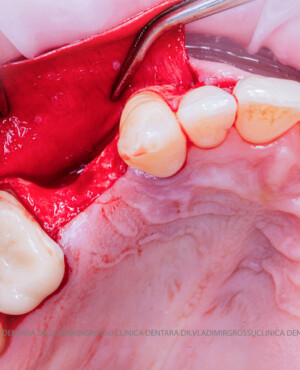

După extracția dentară, în intervalul de 6-12 luni, osul alveolar suferă un proces natural de remodelare, ceea ce conduce la scăderea volumului osos prin rezorbție. De aceea, inserția implantului dentar este ideală imediat după extracție sau, cel târziu, în primele 3-4 luni după aceasta.Scopul procedurilor de adiție osoasă este refacerea fundației osoase necesare pentru stabilizarea corectă a implantului dentar. Pentru ca un implant să reziste în timp la forțele masticatorii, este nevoie de o bază osoasă solidă și sănătoasă.

Adiția osoasă are un rol crucial pentru poziționarea corectă și stabilă a implanturilor dentare. Clinica stomatologică Dr. Grossu din Chișinău promovează o abordare chirurgicală estetică și predictibilă, adaptată fiecărui caz în parte.

Medicii noștri au o vastă experiență atât în chirurgia estetică, cât și în protezarea cu un grad înalt de naturalitate, ceea ce ne permite să gestionăm cu succes și cele mai complexe cazuri.